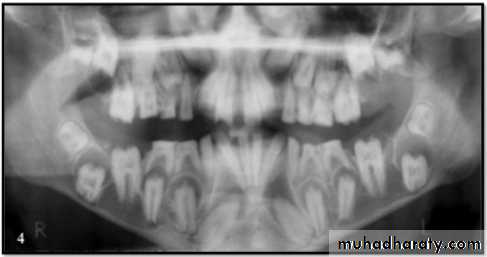

Dentin Dysplasia

Both dentitions are of normal color.

Periapical lesions.Premature tooth loss may occur because of short roots or periapical inflammatory lesions.

Radiographically:

Roots are extremely short.

Pulps almost completely obliterated.

Periapical radiolucencies:

granulomas

cysts

chronic abscesses

Type I (Radicular Type)

Dentin dysplasia, type I. panoramic & periapical films of the same case show the short and poorly developed roots, obliterated pulp chambers and root canals, and periapical inflammatory lesions.

Color of primary dentition is opalescent

Permanent dentition is normal.Coronal pulps are usually large

filled with globules of abnormal dentin.

Deciduous teeth:

roots are extremely short

pulps almost completely obliterated

Permanent teeth:

abnormally large pulp chambers in coronal portion of tooth.

Type II (Coronal Type)

Dentin dysplasia, type II. panoramic &periapical films of the same case show obliteration of the pulp chamber, reduction in the caliber of root canals, and pulp stones obscuring the flame-shaped pulp chambers.

Periapical inflammatory lesions are associated with some of the mandibular anterior teeth.